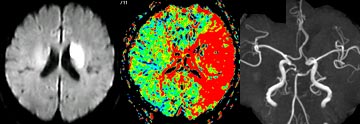

MRI

シーメンス社製(1.5T)の最新装置にて、通常では約20分余りで脳や脊髄(脊椎)などに異常がないかどうか、痛みなどの苦痛なく調べることができます。

造影剤を使用しなくても脳や頚部などの血管を描出でき、まだ脳梗塞に至っていない血管の狭窄や未破裂の脳動脈瘤を発見することもできます。

造影剤を使えば脳循環障害がないかどうかも容易に判定可能です。

・左下:発症60分で脳梗塞が描出(白い部分、拡散強調画像)

・中央:MRIによる脳血流検査(赤い部分が血流低下)

・右下:MRA(脳血管の描出)